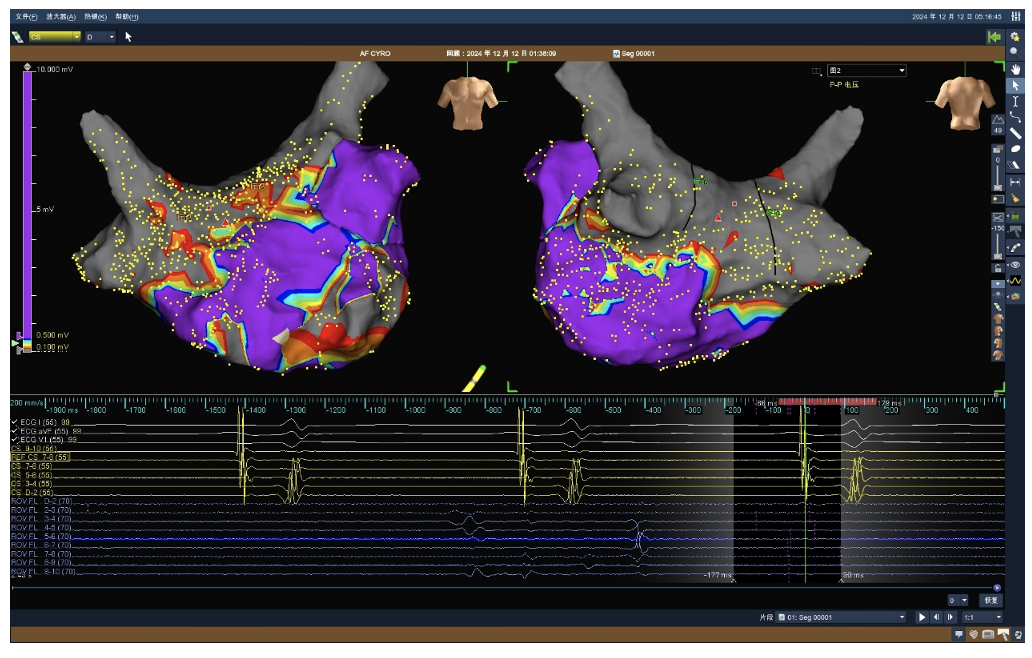

林亚洲主任在三维标测系统的指引下,重建左心房肺静脉三维模型,精准的导航定位脉冲消融导管,手术过程中,平均每根肺静脉放电消融12-15次,整体放电时间仅需30分钟,消融结束后,对患者左房三维基质标测确认消融有效性,均达到理想消融效果。

术后左房电压标测示双侧肺静脉及后壁电隔离